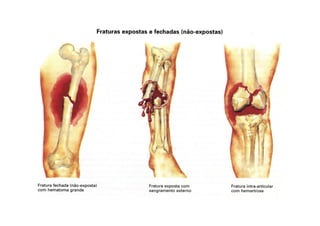

Fratura

• Fratura é a lesão traumática associada à

solução de continuidade do osso.